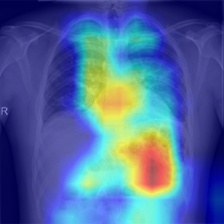

In order to compare the interpretability capacity of our model and the state-of-the-art models, we employ Grad-Cam [18] for heatmap visualizations on selected X-ray images. We show on a side-by-side basis how our model performs with superiority in Figures 4-7. We also observe that the addition of the attention block has a crucial role in focusing on the most relevant features in the images, which significantly assists the model during classification.